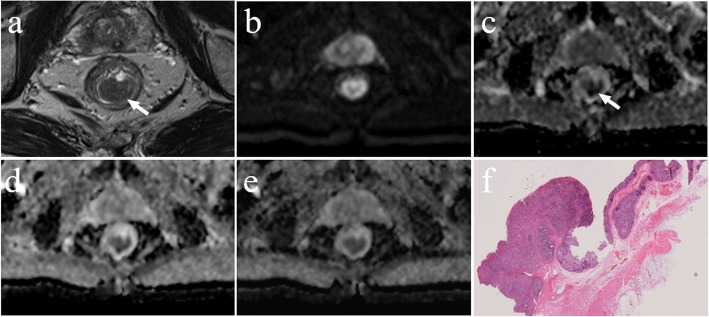

There was a significant negative correlation between the mean ADC values and T stages for patients with rectal cancer in all b-value combinations. The Spearman correlation coefficients for those combinations ranged from − 0.759 to − 0.407. The results of the ROC analysis are shown in Table 2 and Additional file 1: Table S1. Overall, the AUC values ranged between 0.714 and 0.938 for evaluating the mean ADC values and T stages. Representative examples of the images in rectal cancer patients with T1, T2 and T3 stages are shown in Figs. 3, 4, 5, respectively. Figure 6 shows the ROC curves of the mean ADC for discriminating rectal cancer between T1–2 and T3 stages for the representative b-value combinations.

Fig. 3.

A 52-year-old female with moderately differentiated adenocarcinoma (T1 stage). a Axial high resolution T2WI shows the tumour of the posterior rectal wall (arrow). b Diffusion-weighted image at b = 1000 s/mm2. c-e The ADC map shows the lesion with a low-signal-intensity (arrow) at b = 0, 1000 s/mm2, the mean ADC value of the lesion is 1.409 × 10− 3 mm2/s (c). 100, 1000, 1500 s/mm2, the mean ADC value is 1.042 × 10− 3 mm2/s (d). 500, 1500, 2000 s/mm2, the mean ADC value is 0.675 × 10− 3 mm2/s (e). f Postoperative pathology (haematoxylin and eosin, × 1). Tumour cells invaded the submucosa

Fig. 4.

A 58-year-old male with moderately differentiated adenocarcinoma (T2 stage). a Axial high resolution T2WI shows the tumour of the posterior rectal wall (arrow). b Diffusion-weighted image at b = 1000 s/mm2. c-e The ADC map shows the lesion with a low-signal-intensity (arrow) at b = 0, 1000 s/mm2, the mean ADC value of the lesion is 0.999 × 10− 3 mm2/s (c). 100, 1000, 1500 s/mm2, the mean ADC value is 0.832 × 10− 3 mm2/s (d). 500, 1500, 2000 s/mm2, the mean ADC value is 0.647 × 10− 3 mm2/s (e). f Postoperative pathology (haematoxylin and eosin, × 25). Tumour tissue showed papillary and mesh-like alignment. Tumour cells had a cubic and column-like shape with big, atypical, and deeply stained nuclei, which invaded the muscularis propria layer but did not extend beyond it

Fig. 5.

A 59-year-old male with moderately differentiated adenocarcinoma (T3 stage). a Axial high resolution T2WI shows abnormal signals on the front of the intestinal wall. The muscularis propria displayed discontinuity and marginal haziness with a low-signal-intensity (arrow). b Diffusion-weighted image at b = 1000 s/mm2. c-e The ADC map shows the lesion with a low-signal-intensity (arrow) at b = 0, 1000 s/mm2, the mean ADC value of the lesion is 0.737 × 10− 3 mm2/s (c). 100, 1000, 1500 s/mm2, the mean ADC value is 0.597 × 10− 3 mm2/s (d). 500, 1500, 2000 s/mm2, the mean ADC value is 0.513 × 10− 3 mm2/s (e). f Postoperative pathology (haematoxylin and eosin, macro sections, × 1). Tumour tissue shows the muscularis propria is completely disrupted and tumour extension is into the mesorectum